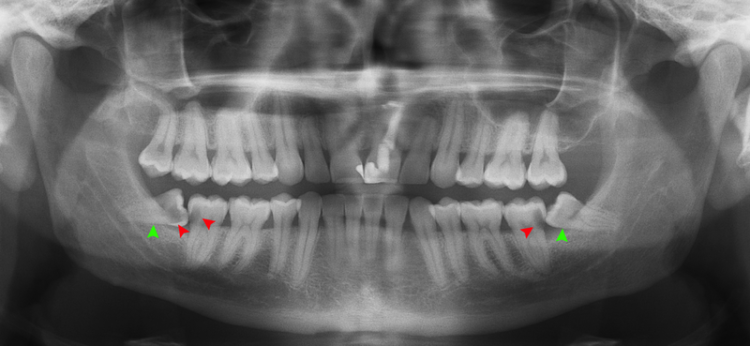

In some cases, however, wisdom teeth may be impacted. I'm getting my wisdom teeth pulled tomorrow, and was surprised to find that instead of the four i thought i had, i actually have five wisdom teeth. Wisdom teeth generally erupt between the ages of 17 and 25.

These molars are more commonly called wisdom teeth. Most problems with wisdom teeth affect people between the ages of 15 and 25. These include infection or delayed healing, both of which are more likely if you smoke during your. Wisdom teeth are an extra set of molars that typically form behind the standard first and second set of molars in the jaw.